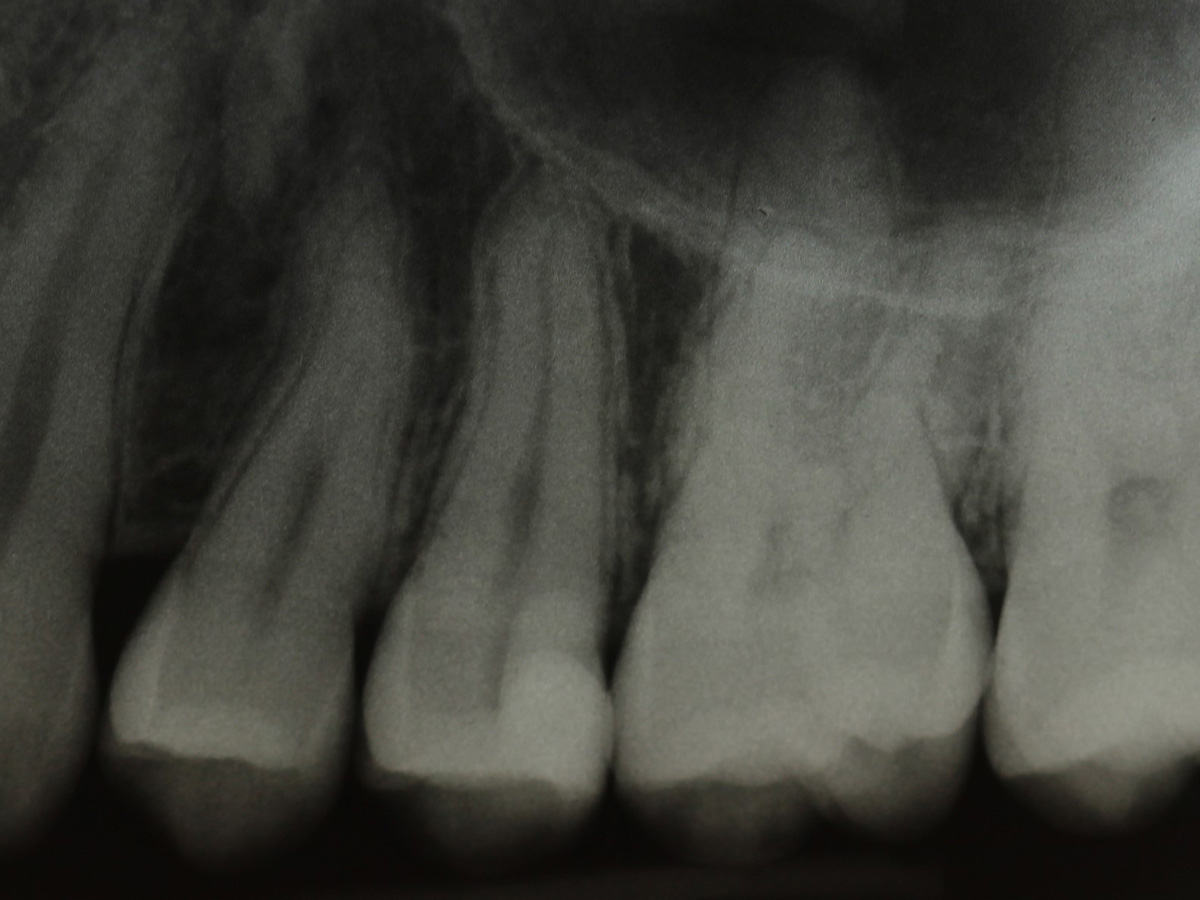

Abbildung 2

Bissflügelröntgenaufnahme

Abbildung 19

Röntgenkontrolle: approximal fast auf Knochenniveau endender spaltfreier Füllungsrand dank interproximaler tieferer Verlängerung der Evolve Matrize